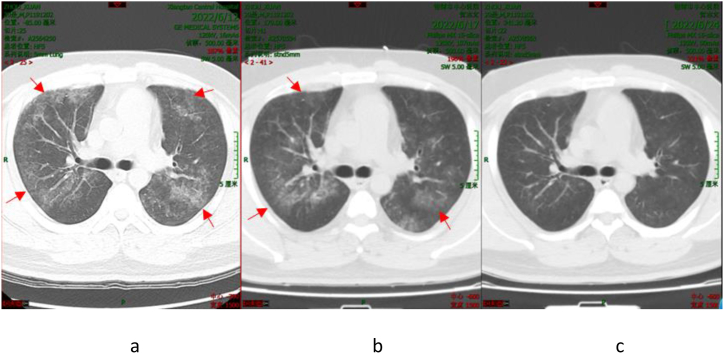

Patient 1 was initially treated empirically with moxifloxacin for 4 days after admission. However unfortunately, the patient showed no improvement in the condition. Consequently, corresponding treatment plan was modified to meropenem combined with doxycycline by the attending physician based on expert opinion. Re-examination of chest CT (Fig. 1(a–c)) revealed significant improvement in lung lesions. Upon discharge, Patient 1 was advised to take doxycycline for an extended period; and the patient coughs occasionally at present.

Fig. 1.

Chest CT Scan of Patient 1 (The dates from left to right: June 12, 2022 (a); June 17, 2022 (b); and June 24, 2022 (c)). The arrowhead shows the focus.